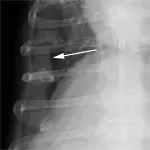

If there is an extrapleural sign, a mass lesion (eg, fractured rib, rib tumor) is pushing the parietal pleura into the pleural space (Figure 4). An anatomic variant that routinely results in an extrapleural sign is the costochondral junction of chondrodystrophic dogs, such as the basset hound or the dachshund.

Extrapleural sign (arrow) in a 10-year old basset hound, secondary to the enlarged costochondral junctions and medial deviation of the costal cartilages